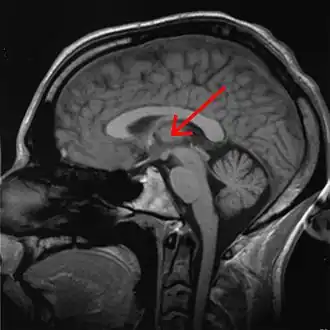

Структурами, контролирующими сенсорную информацию, являются кора больших полушарий (в частности, префронтальная кора, играющая важную роль в контроле внимания), базальные ганглии, ретикулярная формация, таламус (в частности, ретикулярное ядро таламуса) и другие структуры.